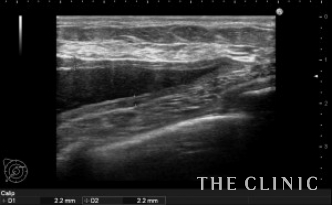

エコーで確認するとかなり厚い被膜が形成されています。

アクアフィリングは生理食塩水で溶解されるとのことで、エコー下に生理食塩水を注入しました。

なかなか溶解できず、ヒアルロニダーゼも追加してなんとか溶解除去することができました。

他にも小さなアクアフィリングのしこりを溶解除去しました。